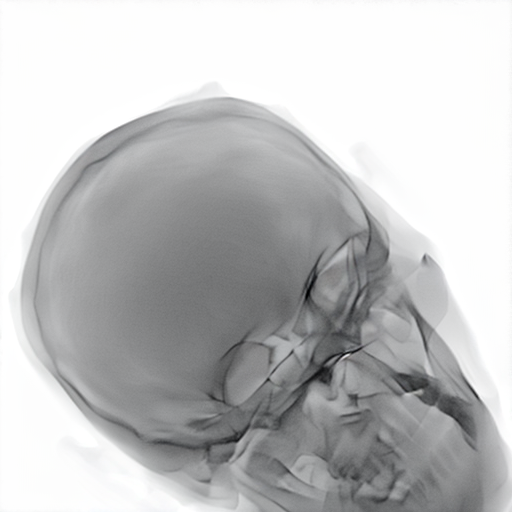

Refer to caption

Figure 2: Dataset overview. The synthetic domain contains Low and High dosage samples generated using the Mentice VIST® simulator; the real domain includes Low, Normal, and Exposure dosage categories acquired from a skull phantom using the Philips Azurion IGT system.

We develop and release a new dataset of real and synthetic head X-ray images, X-DigiSkull, to study the domain adaptation. The dataset consists of synthetic X-ray images of a human skull generated using the Mentice VIST® simulator 111https://www.mentice.com/simulator/vist-g7. Real‑time X‑rays are generated by holding the 3D voxel “patient” head model with per‑voxel attenuation, casting one ray per detector pixel to form a digitally reconstructed radiograph and then approximating scatter, focal‑spot and detector blur, grid/heel effects and detector response, adding quantum/read noise and final image post-processing as the C‑arm and devices move. Real images are acquired from a clinical-grade physical skull phantom using the Philips Azurion Image Guided Therapy (IGT) system. Images are captured from common IGT working positions for neuro procedures. The dataset consists of multiple orientations and is available in three different radiation dose settings: low, normal, and exposure (Philips exclusive), the latter offering enhanced image quality and detail, as shown in Figure 2. This consists of viewing angles rz[40,+40]r_{z}\in[-40^{\circ},+40^{\circ}], ry[40,+40]r_{y}\in[-40^{\circ},+40^{\circ}], rx[40,+40]r_{x}\in[-40^{\circ},+40^{\circ}] with respect to the starting position in 10 increments and up to 3 images at each position to capture the noise present. This results in a total of 2,187 real images. The coordinate systems of the real and synthetic environment are aligned and synthetic images are rendered to approximate the same viewpoints as the real phantom images with the patient table starting at a similar position.The head 3D model used in the simulation is meticulously built from a real clinical case. We capture the synthetic images in finer increments of 5 across the three angles, producing the 5,832 (18318^{3}) images 222Data available at https://zenodo.org/records/16535437. The aim of this alignment is not to achieve precise supervised image translation, but rather to establish a consistent reference structure that preserves spatial features. The composition of the dataset is summarized in Table 1, which contains information on the splits and the number of images available. All images are cropped and resized to 780×\times780 pixels. The test set is obtained by uniformly sampling 15% of viewing angles and corresponding images to ensure a representative distribution. For our experiments, we focus on the task of converting synthetic images at high dose to real images at normal dose.